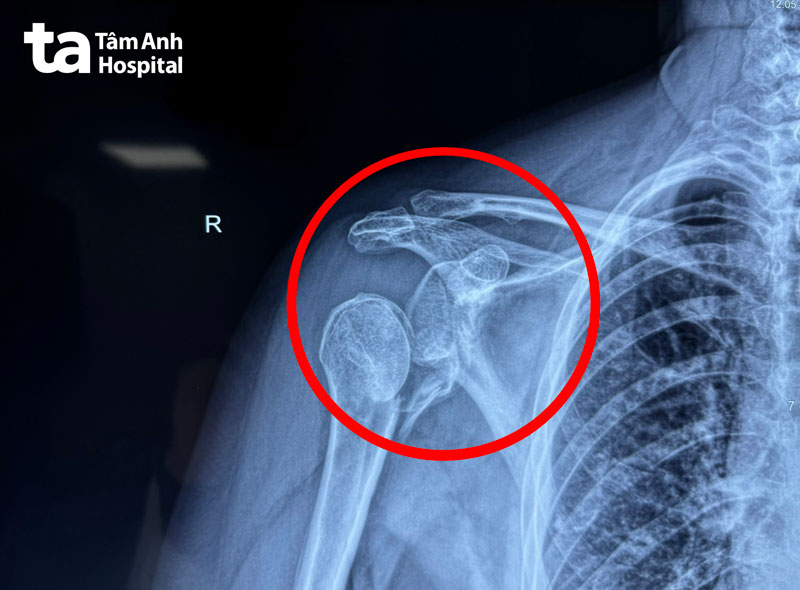

ThS.BS.CKI Mai Hoàng Dương, Trung tâm Chấn thương Chỉnh hình, cho biết người bệnh bị chấn thương khớp vai nặng. Kết quả chụp X-quang và CT cho thấy phần xương ở đầu trên cánh tay đã gãy nát, không thể bảo tồn.

Nếu cố gắng giữ lại khớp vai này, có thể dẫn đến hoại tử chỏm xương và ổ chảo cánh tay, đau đớn kéo dài và giảm nghiêm trọng khả năng vận động. Vì vậy, người bệnh được chỉ định thay khớp vai nhân tạo đảo nghịch bằng đường mổ delta ngực.